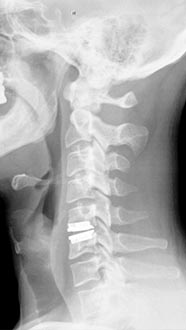

35 year old man presenting with severe neck pain with radiation down the right arm with right bicep weakness. MRI with large right C5-6 disc extrusion.

Postoperative xrays after C5-6 anterior cervical disc replacement. Complete resolution of arm pain and full painless range of motion of his neck.